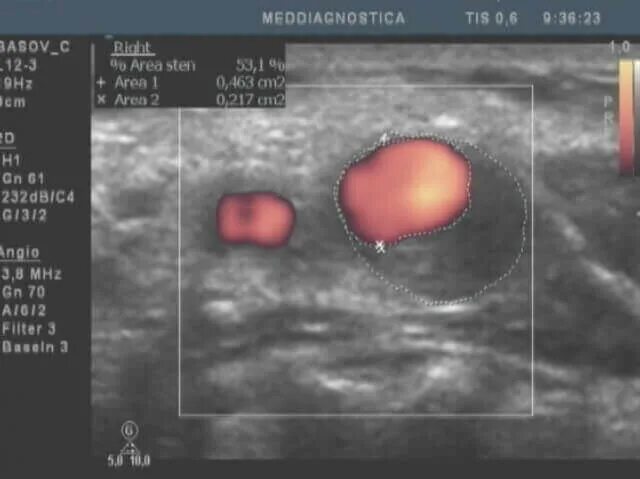

Атеросклероз на узи